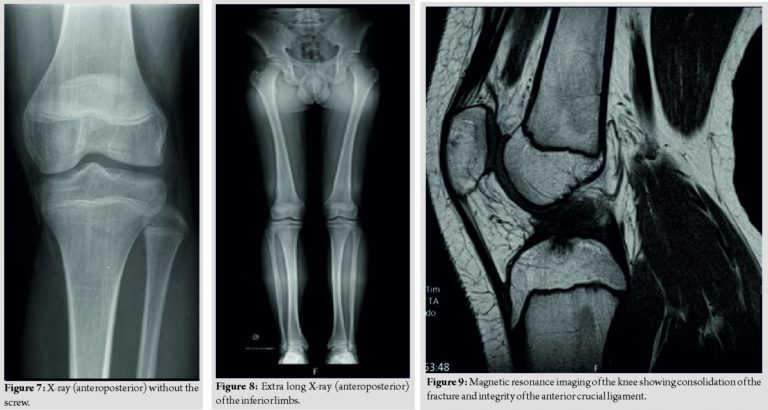

An immobilization of the left arm and forearm was performed. The magnetic resonance imaging of the left forearm revealed “primary bone lesion without invasive features of the soft tissues that can correspond to aneurysmal bone cyst or GCT” (Fig. 3). A biopsy and surgery were proposed. The patient underwent excision and curettage of the lesion with preservation of the periosteum, filling with the left proximal (corpse) allograft and osteosynthesis with plate and screws (Fig. 4).

The anatomopathological examination revealed characteristics compatible with GCT of bone (Fig. 5). The surgery was uneventful and there was no neurovascular injury. The post-operative period was also uneventful. During follow-up, a good clinical and radiological evolution was observed, with consolidation of the lesion (Fig. 6) and recovery of the arch of mobility of the elbow, presenting a deficit of 15° of supination compared to the contralateral side. There was no local recurrence of the lesion and there was no metastization in 2 years of follow-up.